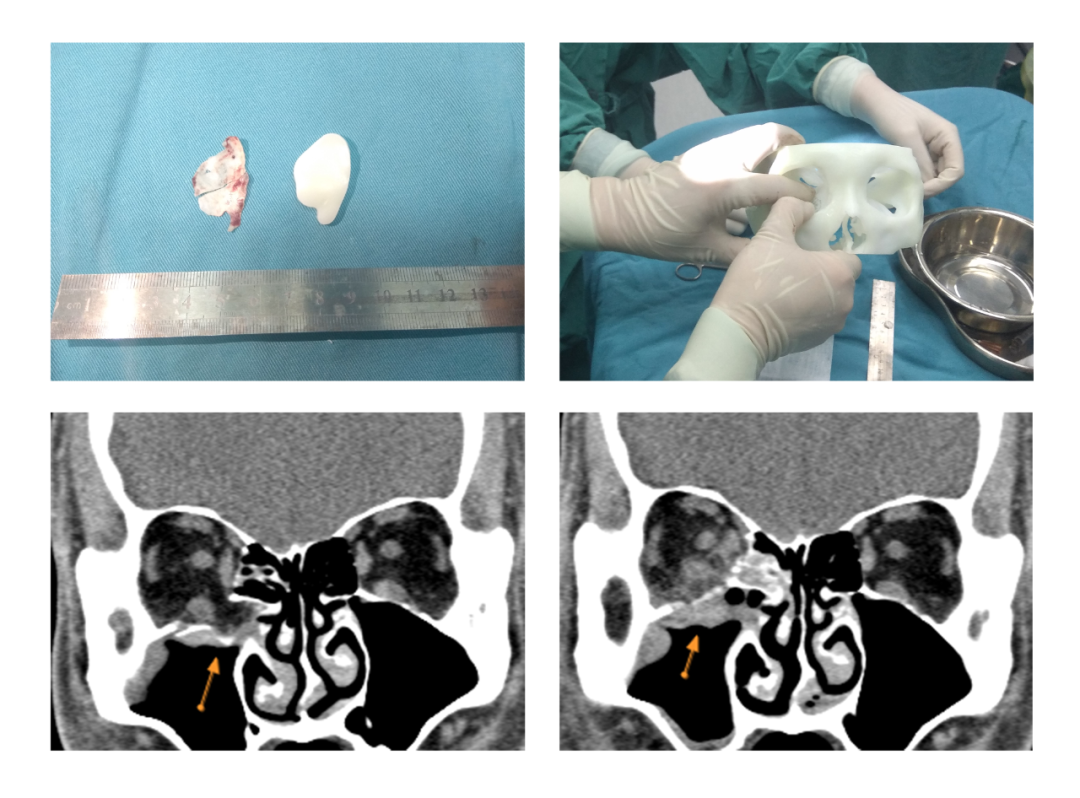

图片图7.术中取出碎骨片与手术导板形态大致相同,参照术前设计的导板裁剪骨折修复材料并用模型进行调试,术前和术后影像学检查中的箭头显示解剖复位已完成。

患者女,42岁,左眼被殴打后视物重影伴眼球内陷8天,左眼外转受限(-1)下转受限(-2),眼突度 :13mm>-96mm-<10mm,影像学提示左眼内壁爆裂性眼眶骨折。给予3D打印导航引导内镜联合可吸收植入物手术整复治疗,术后1周,双眼复视消失,左眼外转受限、下转受限恢复,眼突度 :13mm>-96mm-<12mm。

图8.患者术前、术后CT影像学图片